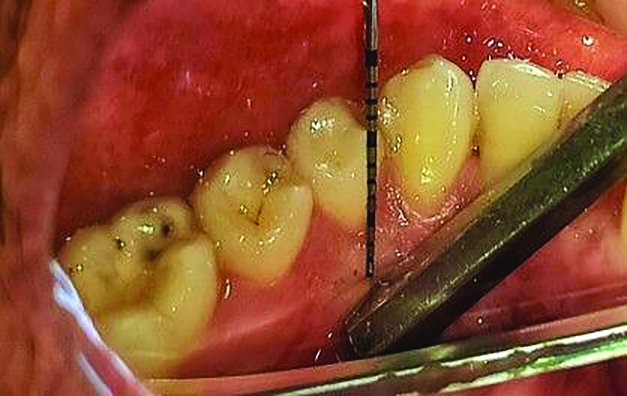

Table 1 presents descriptive statistics for the demographic characteristics of the participants: 83.33% of the study population were aged 18 to 24 years, while 16.66% were aged 25 to 30 years, and 20% of the participants were male while 80% were female, indicating a skewed distribution. Figure 4 through Figure 6 illustrate lingual AG of a representative male subject, and Figure 7 through Figure 9 depict that of a female subject. The mean, standard deviation, mode, median, and extremes for all the mandibular permanent teeth are recorded in Table 2. The extreme measurements were in the range of 0 mm to 10 mm, considering all teeth and subjects. The width of lingual AG varied with each tooth, with the mandibular first molar having the widest average width (6 mm ± 1.3 mm) followed closely by the second molar (5.8 mm ± 1.2 mm). The central incisors (0.5 mm ± 0.5 mm) showed the narrowest zone along with the highest maximum number of teeth without detectable AG (Table 3). The width of AG did not significantly differ between the sexes (Table 4). The overall indicative schematic of lingual AG is shown in Figure 10 and Figure 11.

Fig 4 through Fig 6. Lingual attached gingiva in a male subject: Fig 4 = left side.

Figure 4

Fig 5 = middle.

Figure 5

Fig 6 = right side.

Figure 6